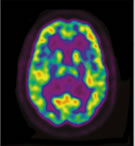

Frontal Lobes

Frontal Lobes Frontal Lobes

Thalamus

Thalamus Thalamus

Neural imaging patterns and EEG research show that TM practice produces a unique state of restful alertness, which can be seen in the decreased activity in the thalamus (the area of the brain that relays input to all other parts of the brain) and increased activity in the frontal and parietal cortices (two areas involved in attention).